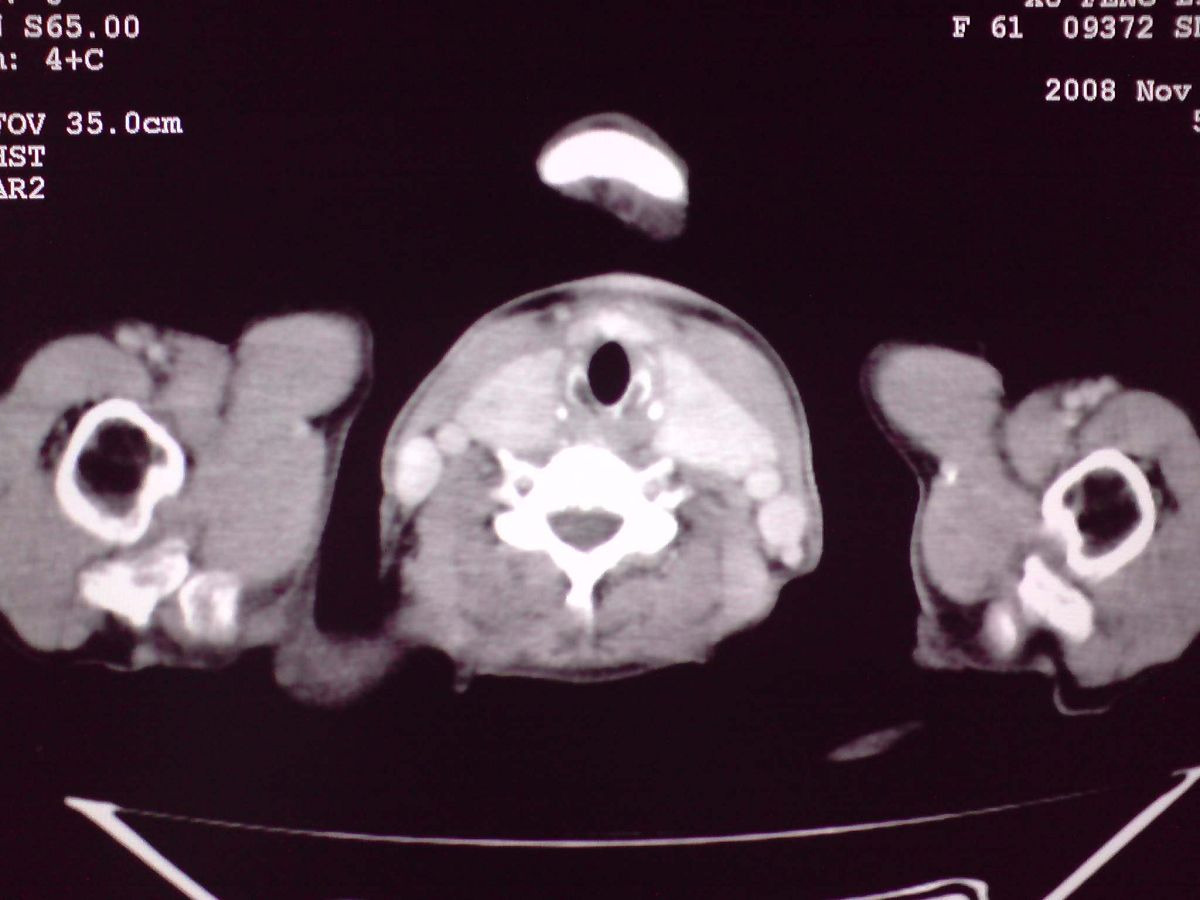

患者女性,65岁,无明显不适,甲状腺功能无异常

结节状甲状腺肿,部分突入胸腔,形成胸内甲状腺

双侧甲状腺肿大,向下部分突入胸腔,双侧甲状腺内密度不均,可见结节状低密度影,并见散在斑点状钙化,增强后病灶实性部分强化明显,气管受压稍变窄左移。

考虑:双侧甲状腺腺瘤可能,不除外甲状腺癌。

胸内甲状腺,双侧结节状甲状腺肿伴右侧甲状腺腺瘤。

甲状腺左右叶增大,并向下突入胸腔内,其内可见多发条片状钙化影及囊性低密度影,邻近组织及血管无浸润、包埋征像,双侧结节性甲状腺肿伴右侧甲状腺腺瘤形成可能性大,甲状腺癌待排;因病人就要手术,期待结果。